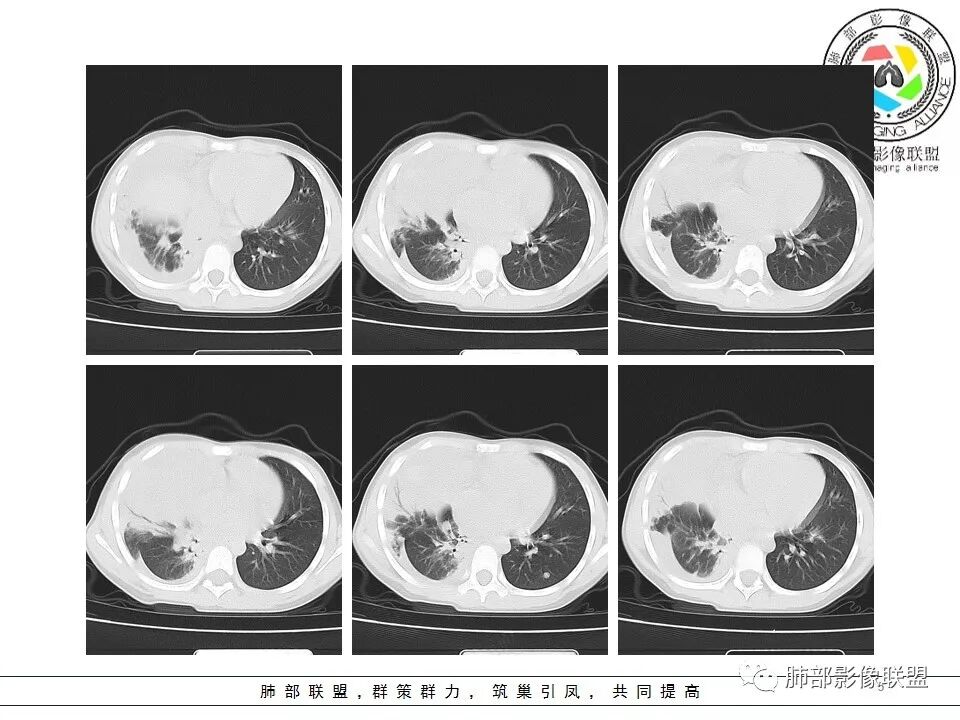

右前纵隔巨大软组织肿块,主要偏向右侧生长,边界不清,密度不均匀,内见大片状低密度坏死区及散在钙化灶,未见骨骼影及脂肪密度影。、双肺随机分布的转移瘤结节,右肺肺不张及右侧胸腔积液,提示恶性肿瘤病变伴双肺及胸膜转移。

前纵隔肿块常见的良性病变为畸胎瘤,恶性肿瘤有侵袭性胸腺瘤或胸腺癌、淋巴瘤、恶性生殖源性肿瘤、Askin(Pnet)瘤等。患儿9岁,30岁以下的胸腺肿瘤非常罕见。而且从病变密度不均,缺乏多结节堆积感,可见钙化等淋巴瘤的可能性不大。虽然这个病例缺乏增强及相关实验室检查,小儿前纵隔恶性肿瘤中恶性生殖细胞肿瘤相对常见,须鉴别的是Askin(Pnet)瘤,可结合有关HCG,AFP和LDH实验室检查帮助甄别。

是高度恶性生殖细胞肿瘤,卵黄囊细胞是唯一产生AFP的细胞,所以AFP升高是卵黄囊瘤或含有卵黄囊成份的生殖细胞肿瘤最重要的特征,其中卵黄囊瘤一般大于1000ug/L;影像表现肿块体积往往较大,易坏死囊变,易侵犯周围结构及转移。

4、绒毛膜癌

纵隔原发性绒毛癌病人几乎为男性,也是高度恶性生殖细胞肿瘤,血、尿β-HCG升高是绒毛膜癌的一个特征,男性乳房发育,影像表现呈分叶状巨大肿块,亦出血坏死,富血供病变,易侵犯血管,所以早期容易出血转移,最常累及的器官为肺。

男性,12岁,绒癌伴双肺转移